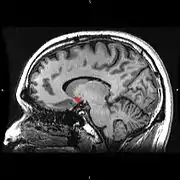

![]() Сагітальна проекція |

| Прилегающее ядро на МРТ головного мозга человека |